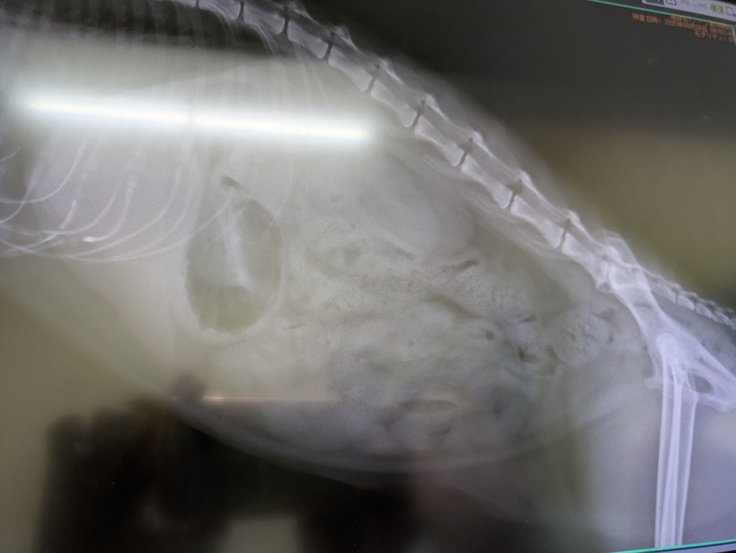

そして本日は[ちゃいろちゃん]の受診日。とても凶暴なので麻酔下で出来る限りの検査をすることになりました。

レントゲンも撮っていただき、若い猫の腎臓と変わらないとのことで問題なし。

膀胱、尿道も全て問題ないとのこと。